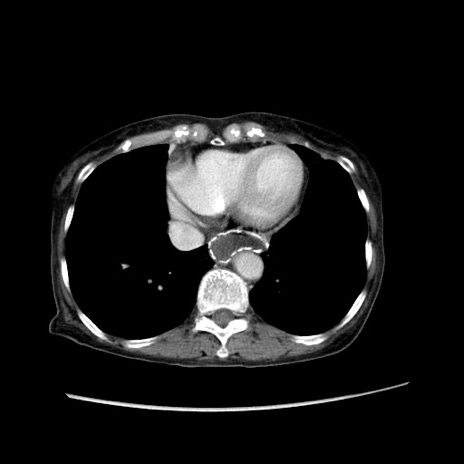

冠状断像

【症例】80歳代女性

【主訴】胸のつかえ感

【現病歴】約9時間前に食後から胸のつかえた感じあり、嘔吐あり、来院。

【既往歴】胃癌(全摘)、胆摘、虫垂炎

【身体所見】心窩部に圧痛あり、反跳痛なし。

【データ】WBC 5700、CRP 0.05